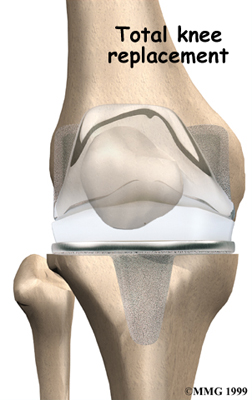

Artificial Knee Replacement

An artificial knee replacement is the ultimate solution for advanced knee OA.

Surgeons prefer not to put a new knee joint in patients younger than 60. This is because younger patients are generally more active and might put too much stress on the joint, causing it to loosen or even crack. A revision surgery to replace a damaged prosthesis is harder to do, has more possible complications, and is usually less successful than a first-time joint replacement surgery.

Related Document: FYZICAL East Lansing's Guide to Artificial Joint Replacement of the Knee